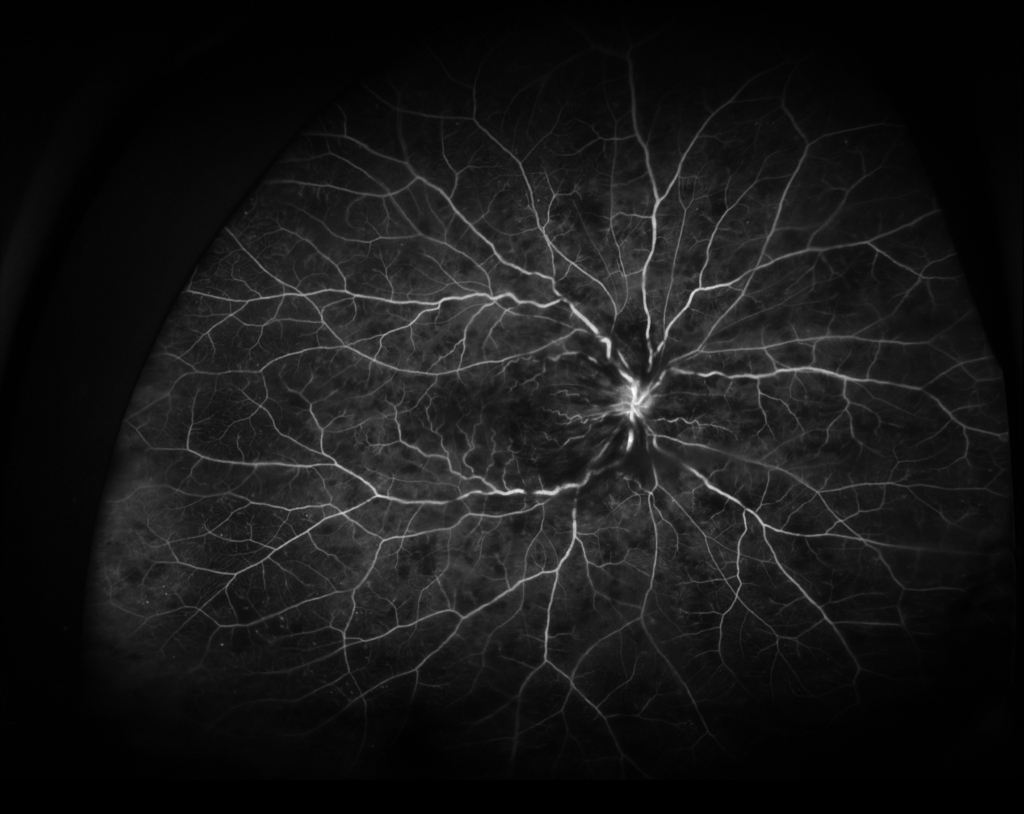

視神経乳頭中心に放射状に静脈に沿って火炎状・線状出血が網膜全体にみられる。